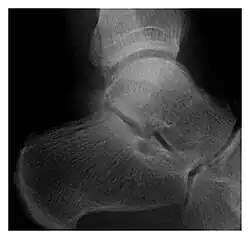

Radiographie d'une fracture de fatigue du talus

Pour vérifier la présence d'une fracture de stress, la radiographie n'est pas toujours efficace au début de la fracture, voire jamais dans certains cas. On peut donc utiliser la scintigraphie osseuse, la tomodensitométrie ou l'IRM[6] pour un diagnostic précoce ; ou la radio standard différée d'une dizaine de jours.